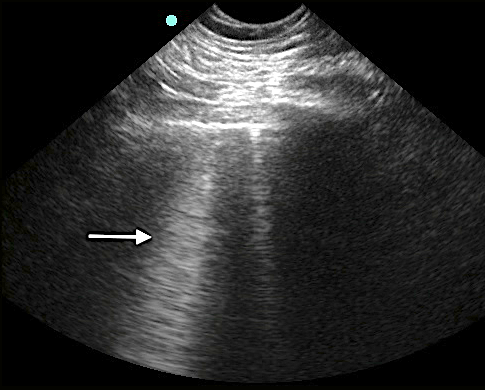

- Vertical hyperechoic comet-tail reverberation artifacts that arise from the pleural line, erase A-lines, move with respiration, and extend to the bottom of the sonographic window without fading.

- Figure 5. B-lines

- Occur due to multiple reflections of sound waves trapped between air and water-rich structures of pulmonary interstitium

- 1-2 B-lines may be detected in dependent regions of normal aerated lung.19

- < 3 B-lines within an intercostal space is considered normal.18, 19

- With increasing density or fluid, more B-lines will appear and coalesce into “lung rockets.”)